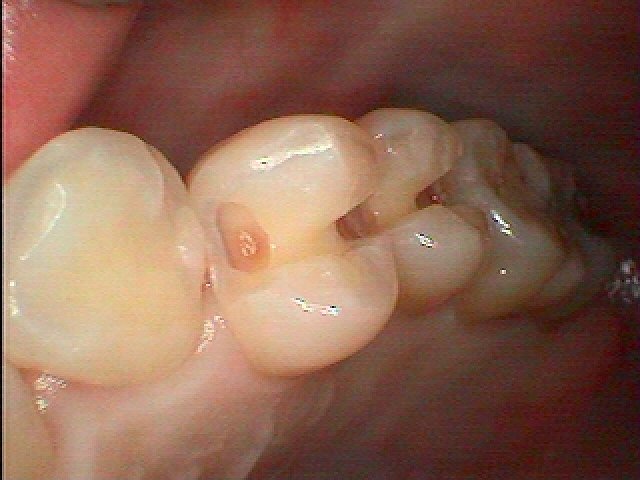

虫歯の治療からセラミックインレーによる審美修復へ。| |広島市安佐南区の歯科医院 虫歯の治療からセラミックインレーによる審美修復へ。 トップ お知らせ・ブログ 虫歯の治療からセラミックインレーによる審美修復へ。 虫歯の治療からセラミックインレーによる審美修復へ。 Web診療予約 初めての方へ 選ばれ続ける理由 院内設備について 歯が痛いしみる一般歯科 歯がぐらぐらする歯周病 健康な歯を保ちたい予防歯科 子供の虫歯予防をしたい小児歯科 銀歯をセラミックに審美歯科 白い歯を目指しませんか?ホワイトニング 矯正専門医がいるので安心矯正歯科 抜けた歯を補いたいインプラント・入れ歯 医院案内 スタッフ紹介 メリィハウス歯科クリニックオフィシャルホームページ ラベンダー歯科クリニックオフィシャルホームページ お知らせ・ブログ ホーム 診療科目 一般歯科 歯周病治療 予防治療 小児歯科 審美治療 ホワイトニング 矯正歯科 入れ歯・インプラント マウスピース矯正 初めての方へ 院長・スタッフ 設備紹介 医院案内・アクセス メニューを閉じる